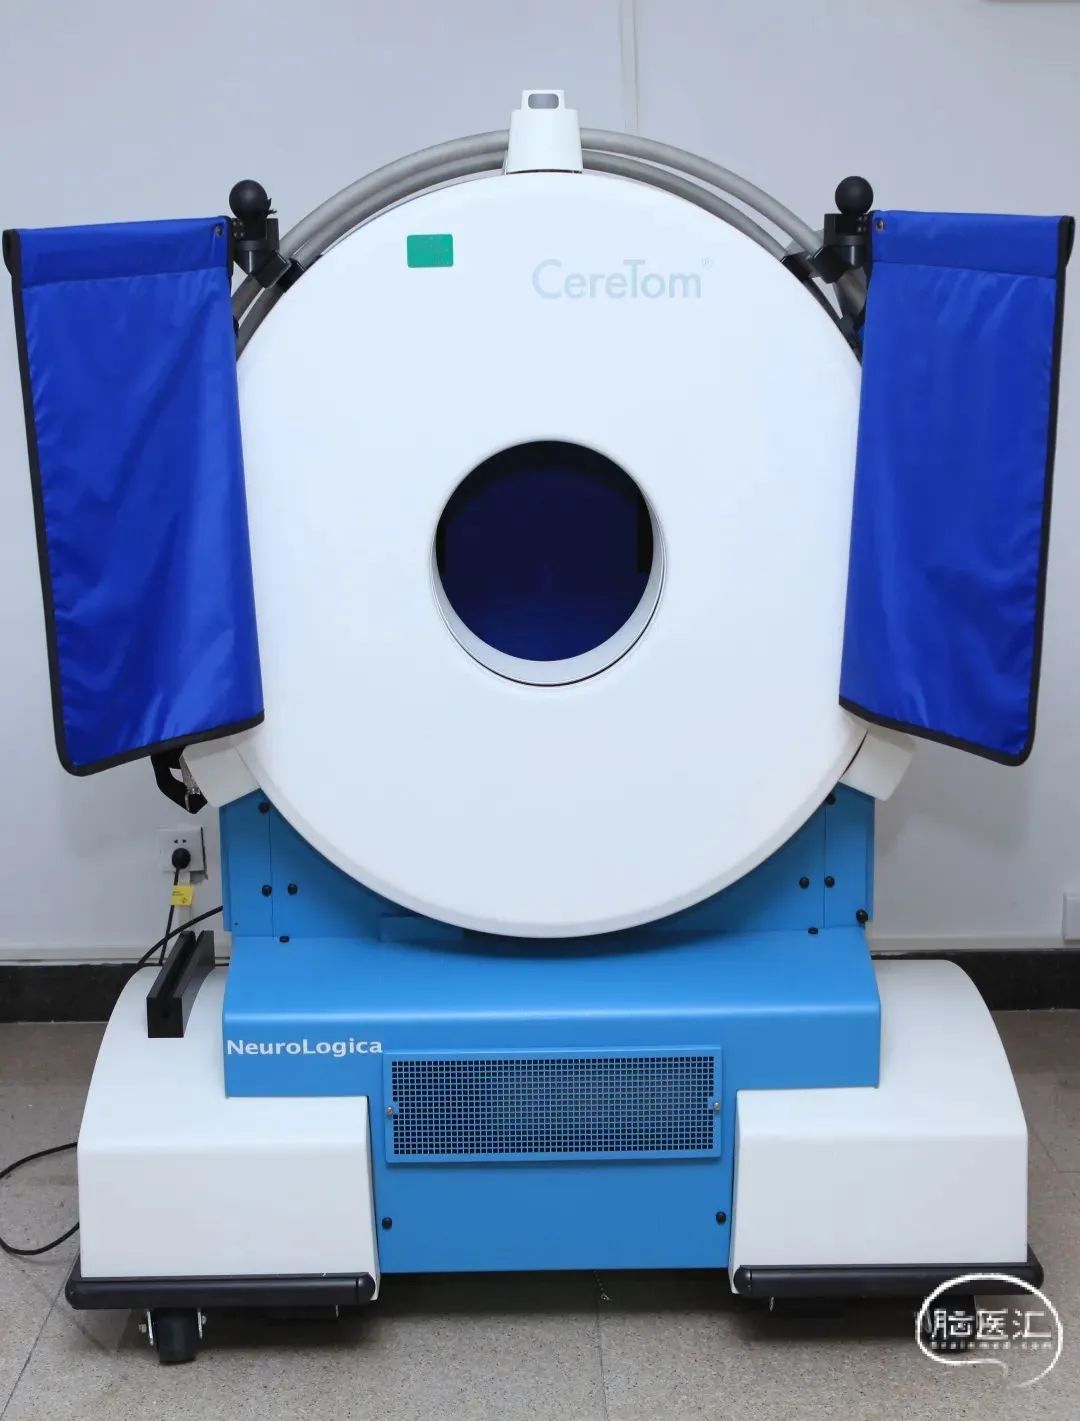

CereTom NL3000 移动式CT